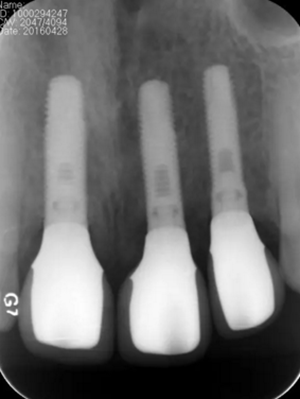

圖13 術(shù)后即刻根尖片

圖17 術(shù)后6個月根尖片

圖24 最終修復(fù)后即刻根尖片